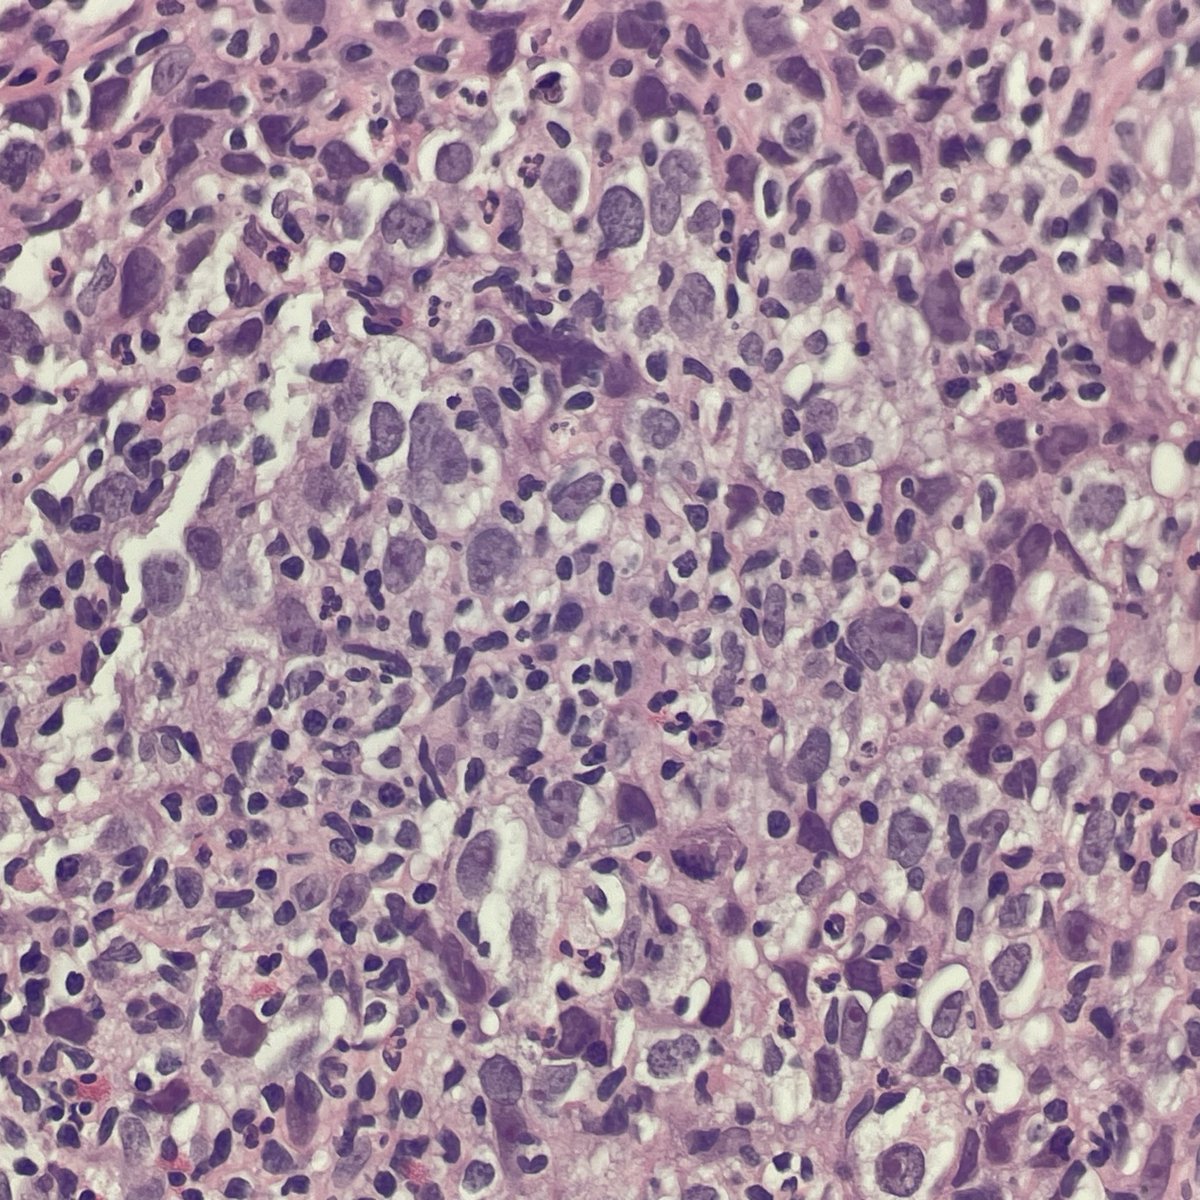

DLBCL, NOS showing signet ring cell-like morphology. #hemepath #PathTwitter